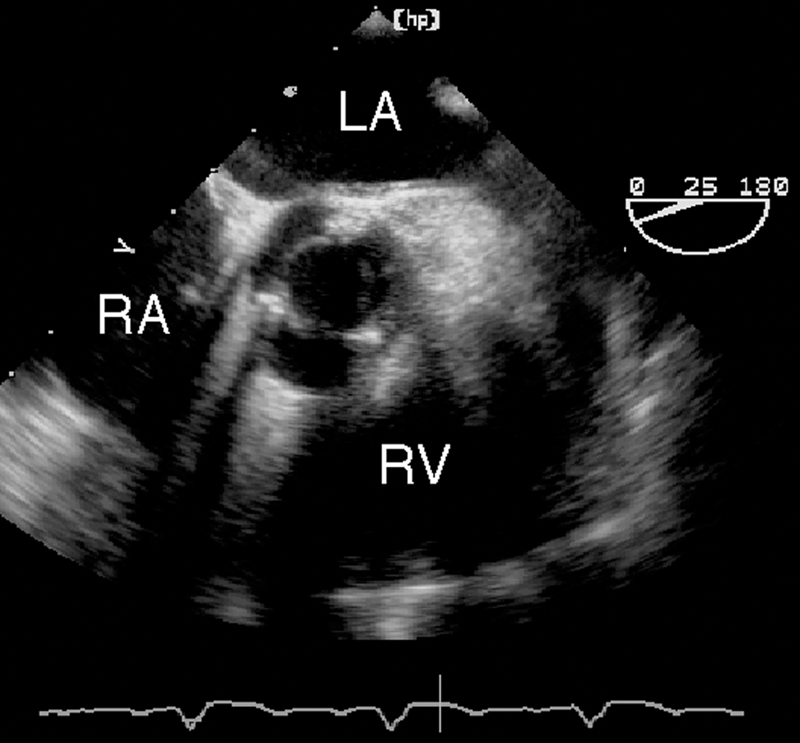

فحوصات تشخيصية لبعض امراض القلب والشرايين التاجية